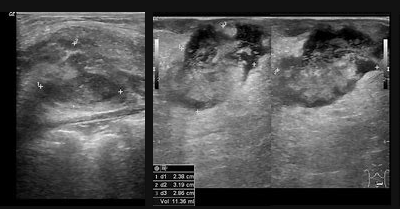

Some pictures of ultrasounds are here. As a layman I'd say, if everything is gray, you're fine, it's those black holes framed in white halos you need to worry about.